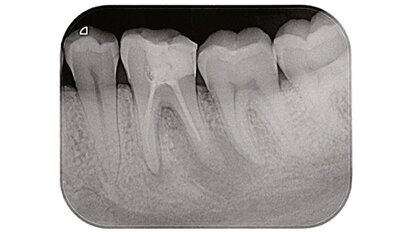

Un’innovativa sistematica per il ritrattamento ortogrado dei canali radicolari: Endo Re-Start (Komet)

Negli ultimi anni c’è stata una crescita importante nel numero dei ritrattamenti endodontici per via ortograda effettuati dai dentisti. Questo aumento di...